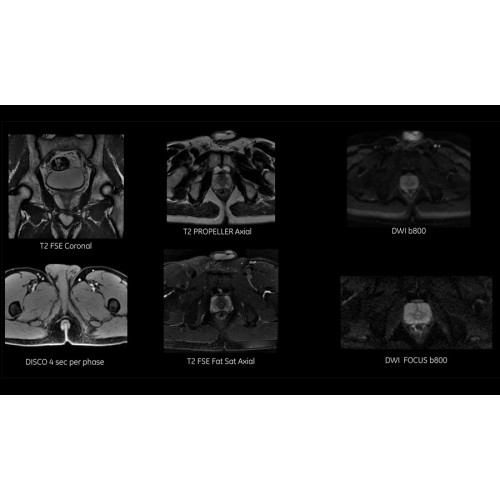

Диагностические возможности аппарата

Многофункциональность исследований

МРТ аппарат GE SIGNA Voyager 1.5T позволяет проводить полный спектр магнитно-резонансных исследований, включая нейровизуализацию, исследования опорно-двигательного аппарата, органов брюшной полости и малого таза, а также специализированные кардиологические программы.

Области применения

• Неврология и нейрохирургия

• Ортопедия и травматология

• Онкологическая диагностика

• Кардиологические исследования

• Обследования органов брюшной полости и малого таза